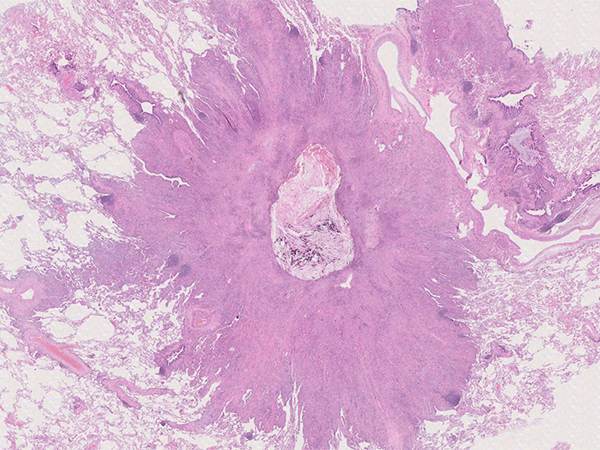

Clinical History: A 1.8-cm solitary peripheral pulmonary nodule was resected in a 72-year-old woman with long-standing rheumatoid arthritis. The clinical suspicion was carcinoma or a rheumatoid nodule. Macroscopically, the nodule was tan-white and lobulated, with central necrosis and calcification as seen in Figure 1. Histologically, the nodule consisted predominantly of cytologically bland histiocytes and multinucleated giant cells with cytoplasmic inclusions and some background fibrosis (Figure 2). The histiocytes were positive for CD163 (Figure 3). The cytoplasmic inclusions were visible as unstained rhomboid/needle-shaped cytoplasmic inclusions in the CD163 stain (Figure 3) and accentuated in the Gram stain (Figure 4).